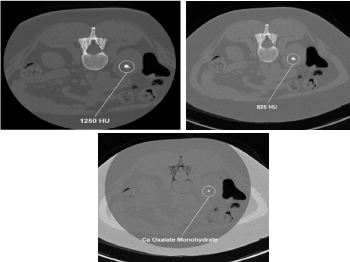

Figure 1. DECT characterization of excretory organ stones. A. DECT axial image shows left excretory organ calculus (stone) with attenuation of 825 HU at one hundred forty kVp. B. This image has 1250 HU attenuation at eighty kVp. C. The stone was firm to be composed of calcium oxalate monohydrate victimization DECT post process algorithms. Reprinted with permission from Coursey CA, Nelson RC, Boll DT, et al. Dual-energy multidetector CT. Radiographic. 2010;30(4): 1045.Uric acids stones demonstrate exaggerated photons attenuation at a hundred and forty kVp as a result of the attenuation is driven primarily by Compton scatter (due to lighter 30% chemical composition).